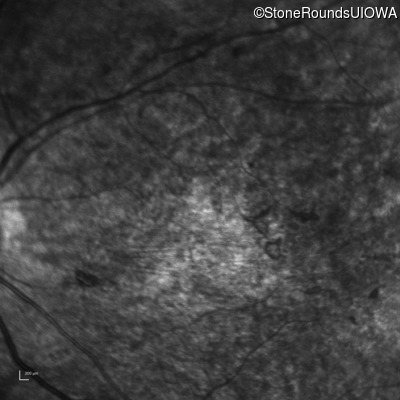

Infrared Fundus Photograph - Right - 10/700 sc

Exemplar